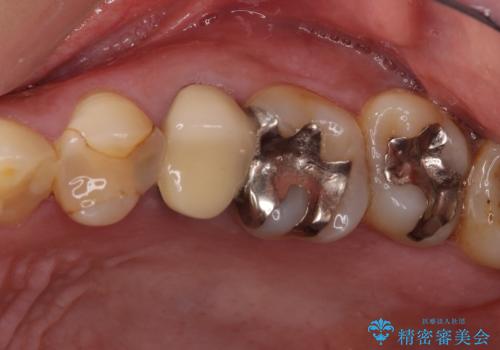

- 右下の欠損部の治療を希望して来院された患者様です。

部分矯正を行った後にインプラント埋入と手前の歯の根管治療を行い、その後補綴治療を行うこととしました。

治療途中より、上の歯や反対側の銀歯、上顎前歯の色合いや下顎前歯のデコボコが気になってきたため、全てを治療することとしました。